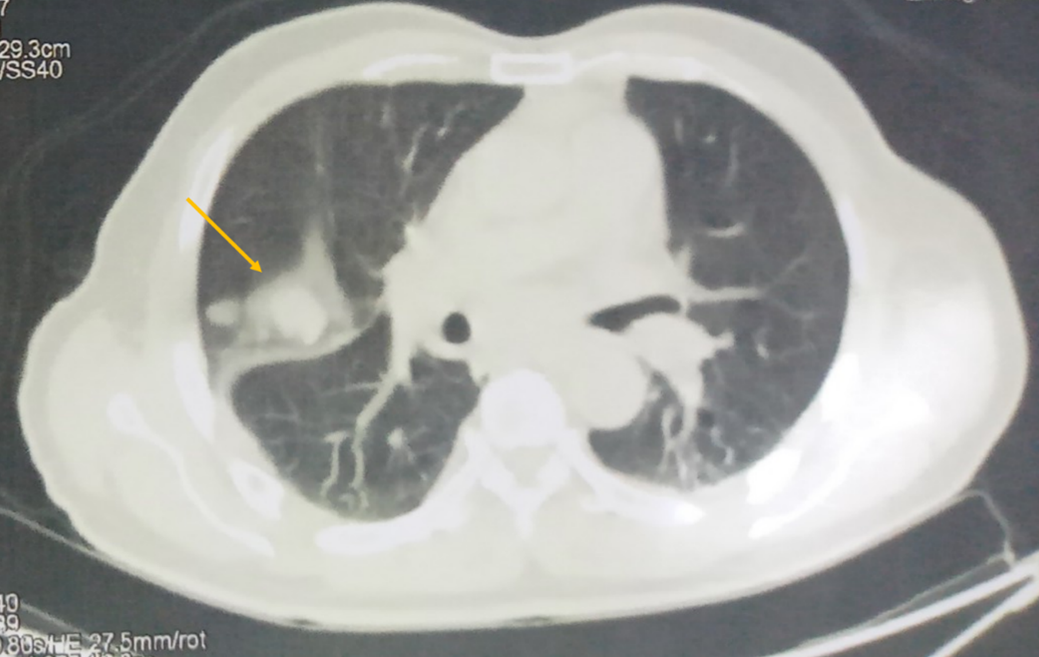

Hình 2: Hình ảnh tổn thương phổi phải không tăng chuyển hoá FDG nhưng chưa loại trừ thứ phát

- Hình ảnh 2 nốt đặc bờ đều ở thuỳ trên phổi phải, kt 19x27 mm và 10x12mm

Hình 6: Không còn thấy tổn thương phổi